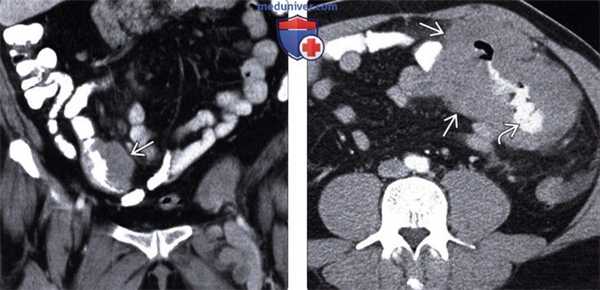

(Слева) УЗИ, поперечная плоскость: визуализировано мягкотканное образование, окружающее аорту и НВП при НХЛ.

(Справа) Бесконтрастная КТ, аксиальная проекция (этот же пациент): пораженные лимфатические узлы при НХЛ заполняют парааортальное пространство и смещают аорту от позвоночника.